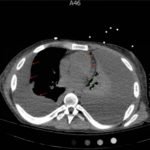

Upright frontal radiograph of the chest demonstrated large pleural effusion on the left and moderate pleural effusion on the right as shown by the visible menisci on both sides (red arrows) with diffuse bilateral nodular densities (yellow dotted lines), consistent with septic pulmonary emboli. Computed tomography (CT) of the chest demonstrated multiple scattered lung nodules bilaterally containing internal foci of air cavitation (green dotted lines).